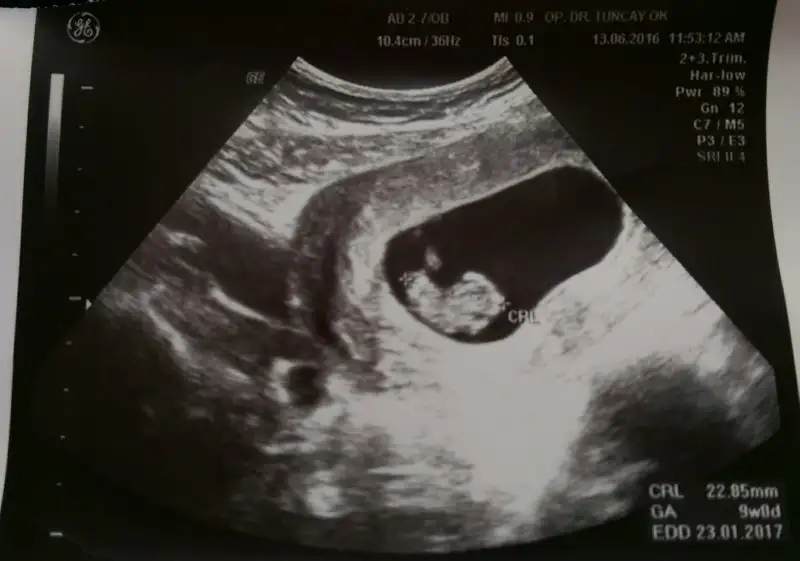

Eki Görüntüle 1847341 bu bebegimin 9 haftalik usg resimi... :) burda ne gibi?